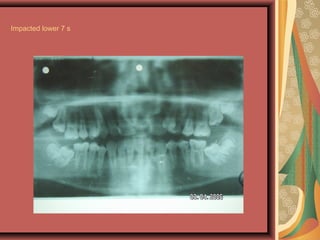

Impacted lower 7 s